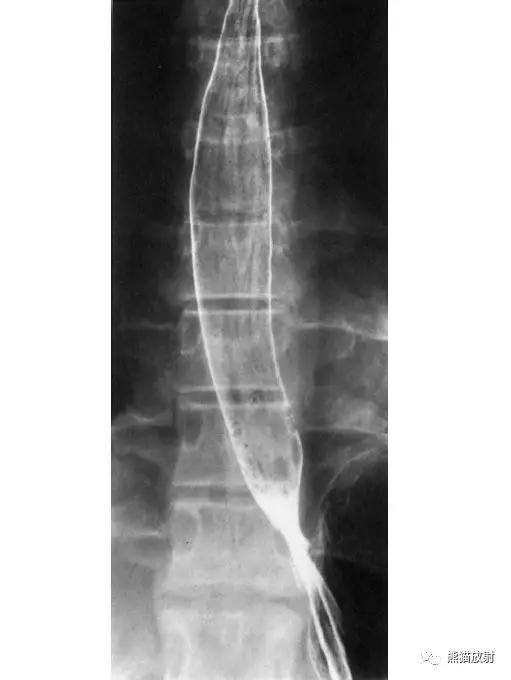

4 Esophagus and Stomach 食管和胃

1 Distal esophagus 食管远段,2 Gastroesophageal angle 胃食管角,3 Abdominal esophagus 食管腹段,4 Esophageal hiatus 食管裂孔,5 Cardia 贲门